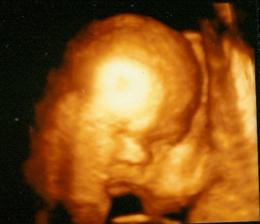

27. týden těhotenství - opět vidíme holčičku, máme za sebou 3D ultrazvuk....